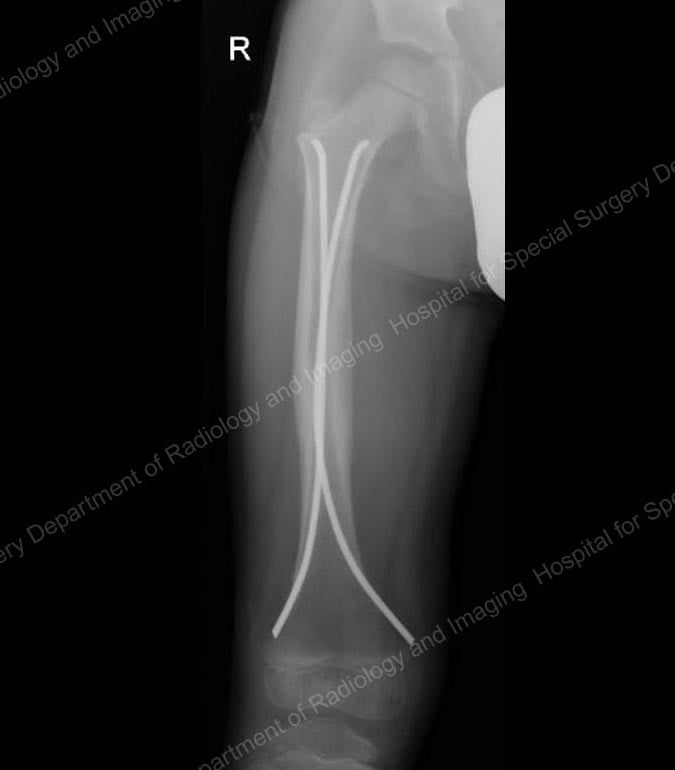

Since the early 2000s, many pediatric orthopedists have started using intramedullary nails or rods made from strong, lightweight, and flexible titanium to stabilize femur fractures in children aged five and older. In a relatively simple technique, the orthopedic surgeon makes two small incisions − about one inch in length − on either side of the knee. After the bone is realigned, the nails are inserted up through the center of the bone where they act as an internal splint during healing.

X-ray showing flexible intramedullary nails in place.

Intramedullary nails come in a range of diameters to accommodate the varying size of children’s bones. Generally no casting is necessary, however a knee immobilizer is commonly used for a few weeks to prevent movement and to keep the child comfortable. In most cases, a recovery period of three to six weeks of early healing is necessary before the child can begin walking on the injured leg. When the bone is completely healed, usually around one year after the injury occurs, the child returns to the hospital to have the nails removed.

Intramedullary nails are usually very well-tolerated. They are particularly useful in five- to ten-year-old children who have a thick lining around the bone called the periosteum, which might be likened to the peel on a banana. The periosteum helps keep the bone more stable and reduces the need for a heavy and rigid device, such as those that might be used in adults.